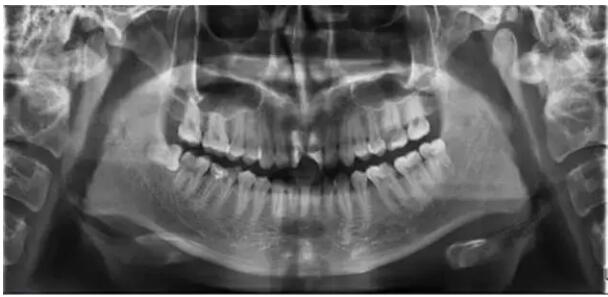

通過(guò)全面詢問(wèn)病史,臨床檢查和拍攝X光片,結(jié)合患者的主觀癥狀、身心狀態(tài),擬定治療方案,充分進(jìn)行醫(yī)患交流并詳細(xì)記錄。

四、確認(rèn)根管工作長(zhǎng)度

應(yīng)用平行投照X線方法、根管長(zhǎng)度測(cè)量?jī)x確定根管長(zhǎng)度 ,最好的辦法是:技術(shù)+經(jīng)驗(yàn)+根管長(zhǎng)度測(cè)量?jī)x+ X線 。